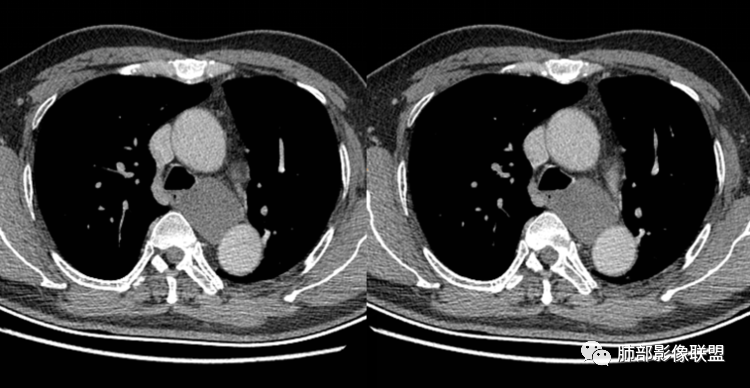

(1)圆形或椭圆形、边缘光滑的病灶,囊壁薄,囊壁可见钙化;由于病变的支气管起源性,囊壁可见属于气管壁的软骨成份.

(2)囊液密度均匀,根据性质的不同而呈不同密度,可为近似水样密度,也可为较高密度,因为囊壁分泌粘液,所以囊内密度一般高于其他纵隔囊肿,CT值多大于20HU甚至超过60HU;

(3)若囊肿内密度较高时与实性肿块鉴别较为困难,增强扫描囊液无强化为鉴别要点;但是囊壁因为含有平滑肌成份,所以可能环形强化;如果病灶合并感染,病灶壁也会明显强化。

(5)张力不高时可以形态柔顺,成份复杂时可以密度较高,但内部不会强化。